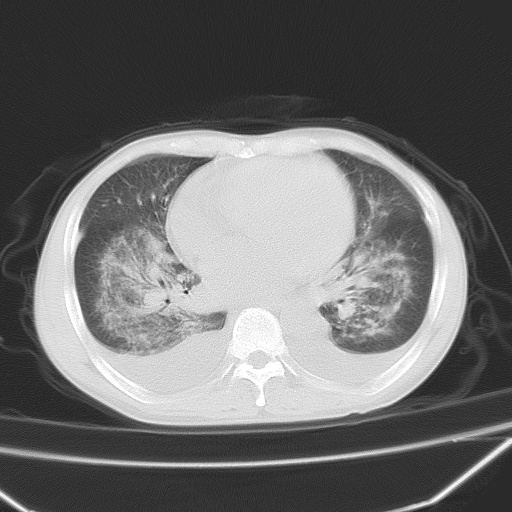

男、42岁、咯血3天。既往有甲亢、贫血、血尿蛋白尿史多年。血象:wbc:6.   中性粒:70.6%。

双肺野对称性磨玻璃影,分布于内中带,双侧胸水,患者有咯血。

双肺野广泛对称性磨玻璃影、实变影,以肺门为中心,主要分布于内中带,符合典型肺泡性肺水肿;伴双侧胸腔少量游离积液。结合患者既往病史且咯血就诊,支持多因素(尿毒症等)所致之肺水肿、肺出血、胸水;影像表现暂不考虑心源性水肿,且症状也不太符。需密切随诊结合临床治疗等进一步明确。